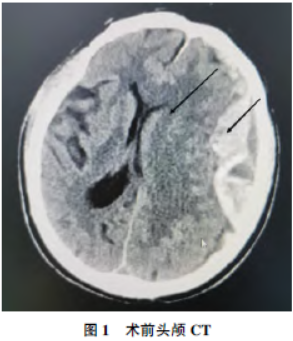

患者,男,78岁,170cm,70kg,因“突发意识不清4h余”入院。患者4h前无明显诱因下突发意识不清,家属呼之不应,伴有小便失禁。送至我院急诊,急查头颅CT示:左侧额颞顶枕部硬膜下血肿,伴脑疝

形成,蛛网膜下腔出血

(图1)。